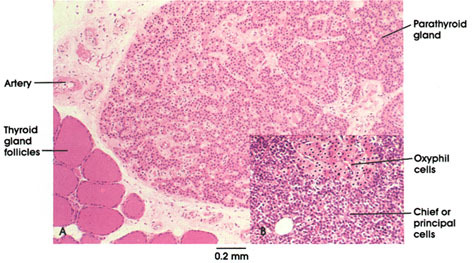

Parathyroidea

Skild från thyroidea av en bindvävssträng

Huvudceller – svagt färgad cytoplasma

Oxyfila celler – ligger i små grupper eller utspridda, större, röd granula

Fettceller